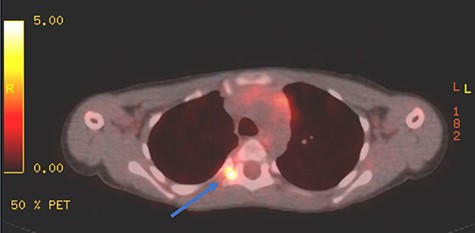

Appropriate tests were done (vanillylmandelic acid and norepinephrine metabolites were found to be slightly high, urine metanephrines were within normal limits, insulin-like growth factor-1 (IGF-1), IGF-binding protein, adrenocorticotropic hormone, cortisol and growth hormone levels were all normal. During her clinic follow-up 6 months post resection, a positron emission tomography (PET) scan showed hypermetabolic activity in the soft tissue at the level of T5 and adjacent right costovertebral junction with possible residual tumor and T5 involvement (Fig. 3). Magnetic resonance imaging was carried out after and showed significant narrowing of the spinal canal at the level of T5 and T6 and focal signal intensity at T5 suggestive of bone involvement (Fig. 4).

PET scan showing area of focal enhancement at the level of the tumor.